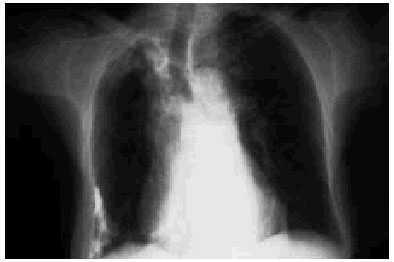

La tuberculosis primaria se manifiesta típicamente como una consolidación parenquimatosa unifocal; la consolidación multilobar es menos frecuente y se observa aproximadamente en el 25% de los casos. En ocasiones el proceso afecta a la totalidad de un lóbulo (a menudo el lóbulo medio). Es posible que este compromiso sea el resultado de una combinación de consolidación del parénquima (causada por invasión directa de los bacilos) y atelectasia (resultante de la obstrucción bronquial debida a compresión extrínseca por adenopatías o a proceso endobronquial) (fig. 1).

Fig. 1. Tuberculosis pulmonar primaria. La radiografía de tórax frontal revela una consolidación parenquimatosa unifocal y adenopatías paratraqueales derechas (flecha negra) y posiblemente hiliares ipsolaterales.